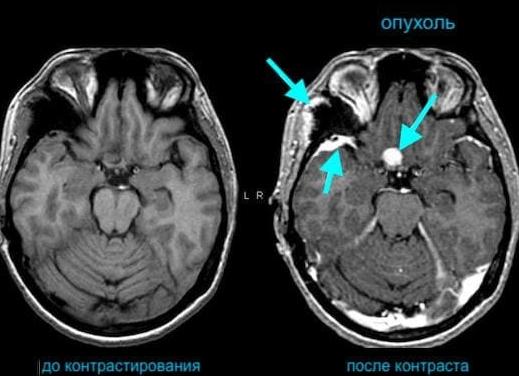

Если болезнь относится к онкологии, обязательно проводят МРТ с контрастом. То же самое касается и рассеянного склероза, и диагностики изменений сосудов в головном мозге. Контрастное вещество помогает четче увидеть, на какой стадии находится опухолевый процесс, и к какой категории относить новообразование. Как правило, злокачественная опухоль вберет в себя большее количество контрастного раствора, поэтому на рисунке можно в мельчайших деталях ее рассмотреть. И это позволяет врачу расшифровать картинку максимально точно.

Однако в некоторых ситуациях обследования обычным магнитно-резонансным способом недостаточно. Особенно часто это случается при поражениях головного мозга. Для улучшения качества изображения столь важного для человека органа дополнительно вводят контрастные вещества, основанные на солях гадолиния – Дотарем, Гадовист, Омнискан, Примовист.

Контрастный раствор вводят пациенту внутривенно перед началом диагностического обследования для получения более объемного и четкого изображения органа. Данное вещество выполняет роль индикатора изменений, происходящих в головном мозге – оно активно накапливается в зоне очага патологического процесса.

Контраст обладает способностью «подсвечивать» ткани, это явление фиксирует чувствительное медицинское оборудование. Магнитное поле, воздействующее на красящий препарат, позволяет получить более четкую визуализацию исследуемой области человеческого тела. Скорость распространения вещества по сосудистой системе находится в зависимости от интенсивности кровообращения в месте обследования.

Это вещество не вызывает аллергическую реакцию и легко выводится из организма пациента. Его уникальность заключается в способности «подсвечивать» сосуды и ткани, что предоставляет возможность специалистам более подробно изучить исследуемые ткани. А это играет значительную роль в выявлении злокачественных опухолей! Благодаря использованию магнитной томографии с контрастным веществом значительно выросли возможности диагностирования патологий головного мозга, скрытых внутренних кровотечений и воспалительных процессов.

Парамагнетические контрастные вещества вместе кровью распространяются по сосудам. Под воздействием контраста цветовая интенсивность увеличивается, и врач может с точностью выявить размеры и границы патологий или структуру злокачественных/доброкачественных новообразований. Без контраста специалист просто не заметит на снимках изменения, поскольку их не будет видно.

Инъекция контраста внутривенно в большинстве случаев выполняется после предварительного выполнения «не контрастных» снимков. Лаборант вводит в вену на руке пациента небольшое количество контрастного вещества (не более 20 миллилитров). После чего снова проводиться процедура магнитно резонансного исследования. Таким образом, врач, сравнивая снимки с контрастом и без, получает максимум информации о конкретном участке тела пациента и может поставить правильный диагноз.